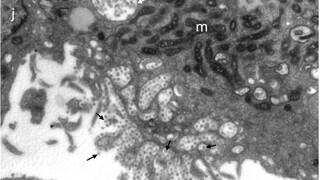

14:07 Takto vyzerá "náš" koronavírus. Vedcom zo Slovenskej akadémie vied sa pomocou elektrónovej mikroskopie podarilo vizualizovať vírusové častice koronavírusu SARS-CoV-2, ktoré boli izolované zo slovenských pacientov s Covidom-19. ⁠